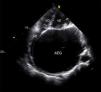

O ecocardiograma revelou uma aurícula esquerda gigante (AEG), com diâmetro ântero‐posterior de 10,5cm e volume indexado à superfície corporal de 1.054mL/m2 (Figura 2, vídeo 1); válvula mitral com abertura em cúpula sugestiva de etiologia reumática (vídeo 2) com regurgitação e estenose graves; regurgitação tricúspide grave e pressão sistólica na artéria pulmonar de 74mmHg.

Vídeo 1. Ecocardiograma transtorácico, plano apical quatro câmaras. É evidente a aurícula esquerda gigante que comprime e altera a geometria das restantes cavidades.